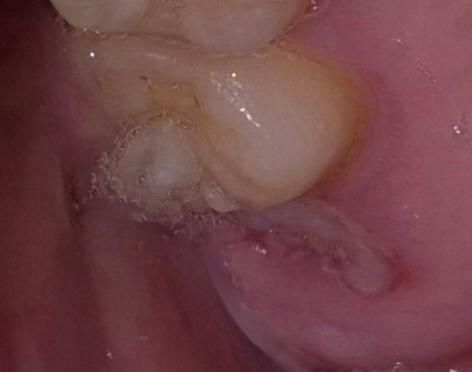

매복 사랑니가 난거 같은데 발치해야 하나요?

아까부터 윗니 어금니 뒤쪽이 아프길래 손톱으로 찔렀더니 이가 드러났는데 알고보니 사랑니였네요..그래서 질문할게 있습니다

1.사랑니가 예시 이미지와 같이 자랐나요?

• 1번 째 사진

매복사랑니가 자라나고 있는 것으로 보이며 발치를 하는 것이 좋아보입니다. 다른 치아에 문제를 일으킬 수 있습니다.

사랑니가 노출되면서 염증이 생길가능성이 높으니 치과에 가셔서 확인후 발치를 하시는게 좋을것같습니다.